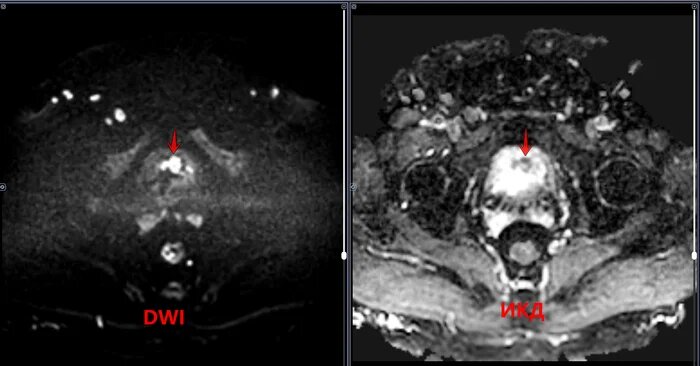

Мочевой пузырь заполнен умеренно, стенки его неравномерно утолщены, в полости визуализируется объемное солидное образования, с четкими, бугристыми контурами, исходящие: из левой боковой и частично задней стенок на 12-18 часах условного циферблата в аксиально проекции, прорастающее все стенки мочевого пузыря с микроскопической тяжистостью окружающей паравезикальной клетчатки слева, с деформацией стенок мочевого пузыря, с зонами ограничения диффузии(гиперсигнал на DWI, гипо на ИКД) во внутренних отделах образования. Предстательная железа увеличена в объеме-признак ДГПЖ. Категория годности с диагнозом рак мочевого пузыря по ст.8(Злокачественные новообразования (кроме злокачественных новообразований лимфоидной, кроветворной и родственных им тканей):а-Д(не годен к в/сл) по I, II, III графе.

Мочевой пузырь заполнен умеренно, стенки его неравномерно утолщены, в полости визуализируется объемное солидное образования, с четкими, бугристыми контурами, исходящие: из левой боковой и частично задней стенок на 12-18 часах условного циферблата в аксиально проекции, прорастающее все стенки мочевого пузыря с микроскопической тяжистостью окружающей паравезикальной клетчатки слева, с деформацией стенок мочевого пузыря, с зонами ограничения диффузии(гиперсигнал на DWI, гипо на ИКД) во внутренних отделах образования. Предстательная железа увеличена в объеме-признак ДГПЖ.